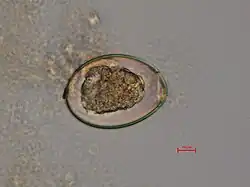

The adult worm is composed of three fairly distinct morphological segments: the scolex (head), the neck, and the lower body. Each side of the scolex has a slit-like groove, which is a bothrium for attachment to the intestine. The scolex attaches to the neck, or proliferative region. From the neck grow many proglottid segments which contain the reproductive organs of the worm. D. latum is the longest tapeworm in humans, averaging ten meters long. Unlike many other tapeworms, Diphyllobothrium eggs are typically unembryonated when passed in human feces.[4]

Because humans do not generally eat undercooked minnows and similar small freshwater fish, these do not represent an important source of infection. Nevertheless, these small second intermediate hosts can be eaten by larger predator species, for example trout, perch, walleye, and pike. In this case, the sparganum can migrate to the musculature of the larger predator fish and mammals can acquire the disease by eating these later intermediate infected host fish raw or undercooked. After ingestion of the infected fish, the plerocercoids develop into immature adults and then into mature adult tapeworms which will reside in the small intestine. The adults attach to the intestinal mucosa by means of the two bilateral grooves (bothria) of their scolices. The adults can reach more than 10 m (up to 30 ft) in length in some species such as D. latum, with more than 3,000 proglottids. One or several of the tape-like proglottid segments (hence the name tapeworm) regularly detach from the main body of the worm and release immature eggs in freshwater to start the cycle over again. Immature eggs are discharged from the proglottids (up to 1,000,000 eggs per day per worm) and are passed in the feces. The incubation period in humans, after which eggs begin to appear in the feces is typically 4–6 weeks, but can vary from as short as 2 weeks to as long as 2 years.[8]